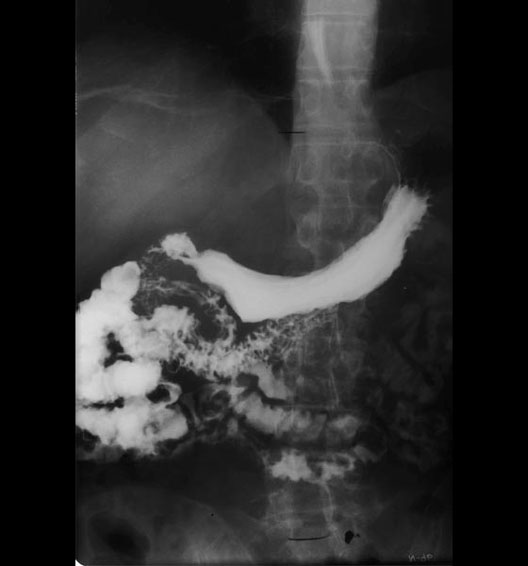

Barium Swallow

1. Lesser Curvature

2. First part of the duodenum

3. Pyloric orifice

4. Pyloric canal

5. Small bowel

6. Pyloric antrum

7. Fundus of stomach

8. Body of stomach

9. Greater Curvature